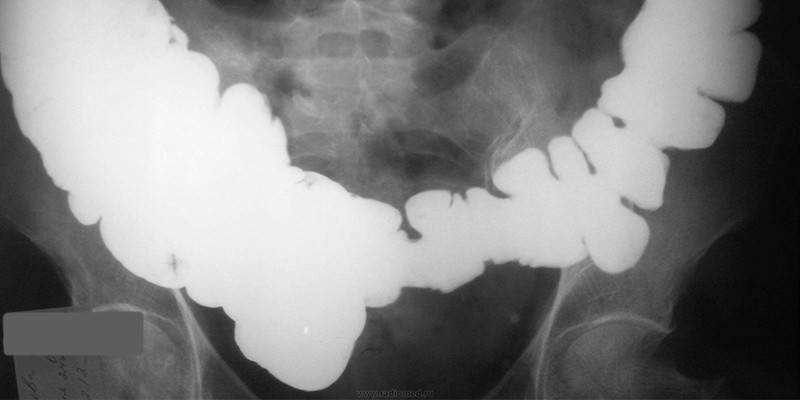

- irrigografia - raio-x do intestino com a introdução de bário;